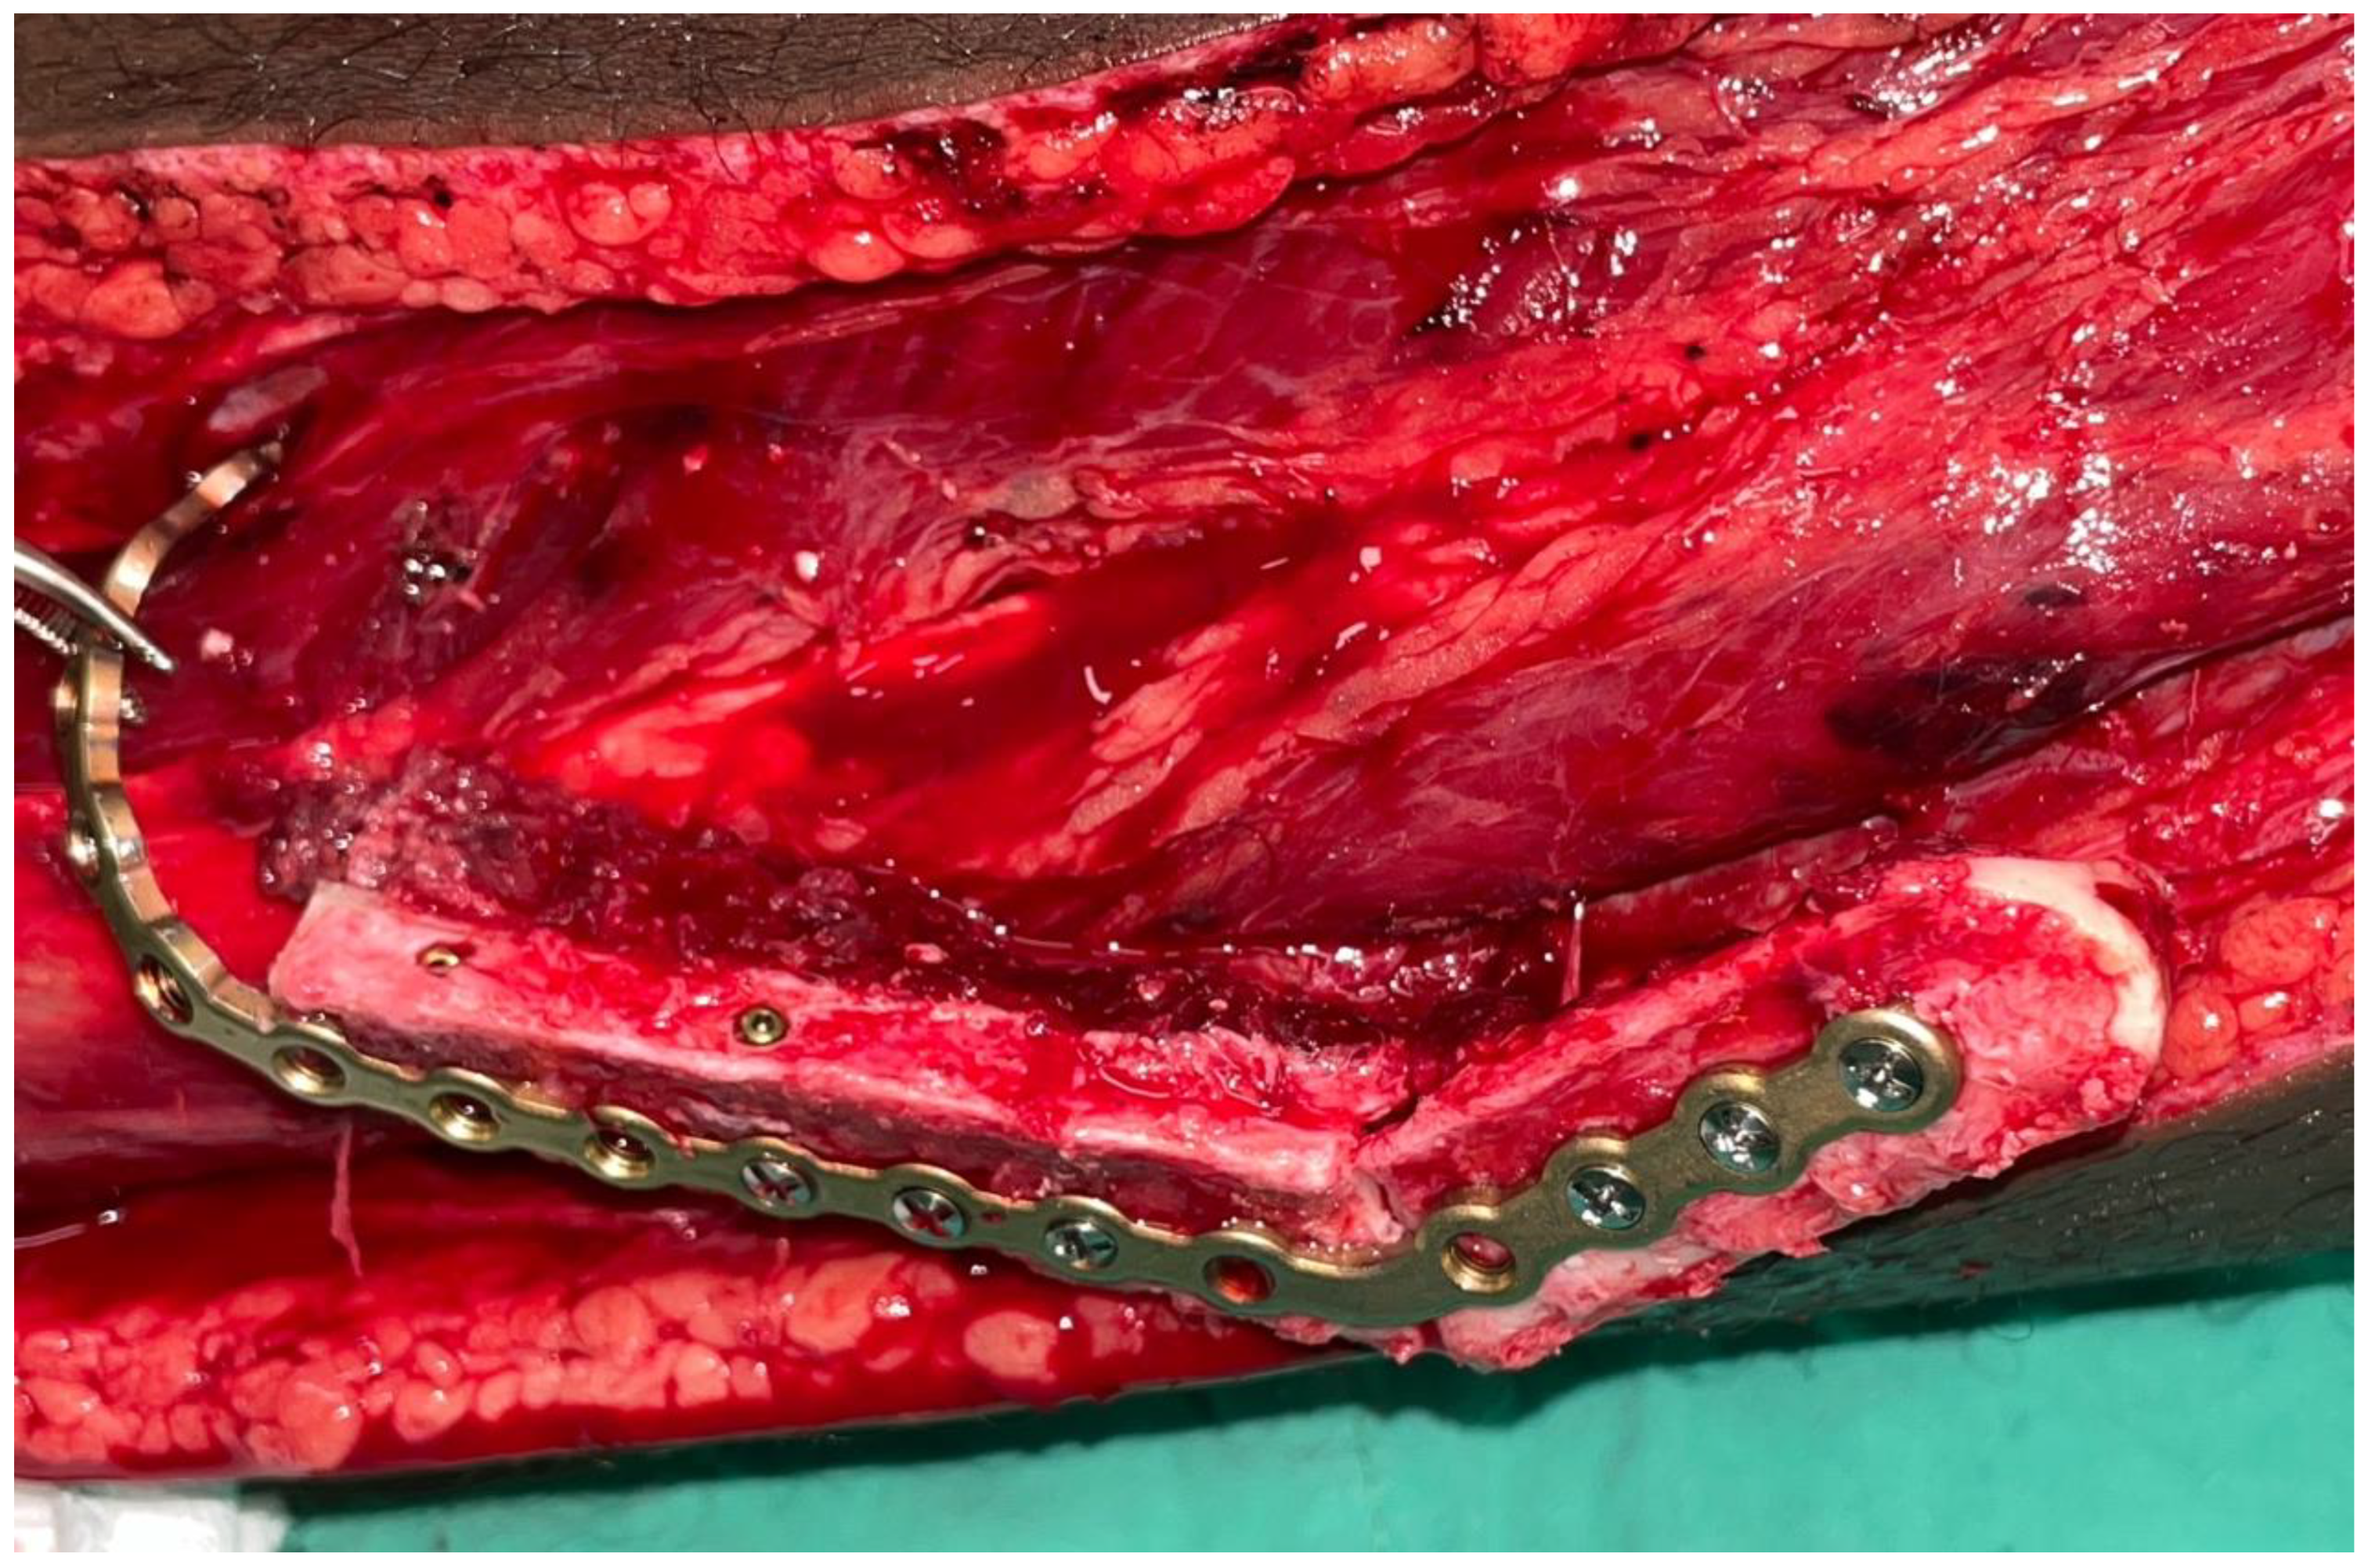

2.1. Case 1

2.2. Case 2